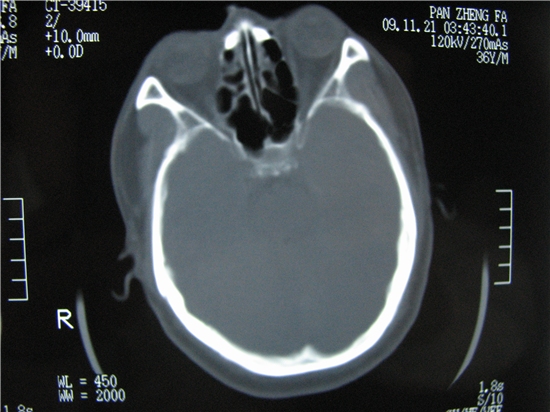

标题: CT23231:男 32岁 车祸伤,鼻腔内出血明显。 [打印本页]

标题: CT23231:男 32岁 车祸伤,鼻腔内出血明显。

不排除鼻骨骨折!

鼻骨层面较少,无法判断鼻骨。

建议薄扫一下。

左侧额骨、鼻骨骨折,头面部软组织肿胀。

左侧额骨、鼻骨骨折,额窦内的应该是游离骨块